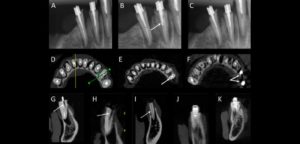

Las fracturas radiculares verticales (VRFs) representan aproximadamente el 2-5% de todas las fracturas dentales y están presentes en el 10-20% de los dientes extraídos que